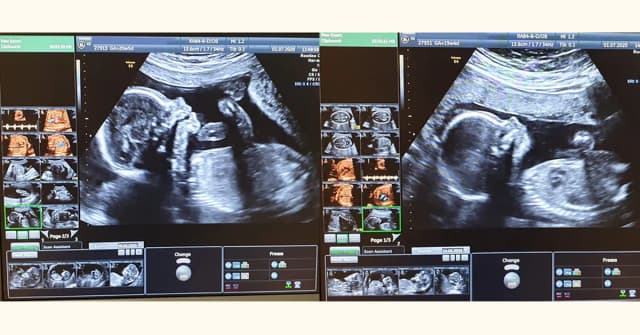

Czy badania prenatalne są obowiązkowe? Poznaj istotne informacje i zmiany.

Dowiedz się, czy badania prenatalne są obowiązkowe w Polsce. Poznaj rodzaje badań w ciąży, ich znaczenie oraz aktualne zalecenia dotyczące zdrowia matki i dziecka.